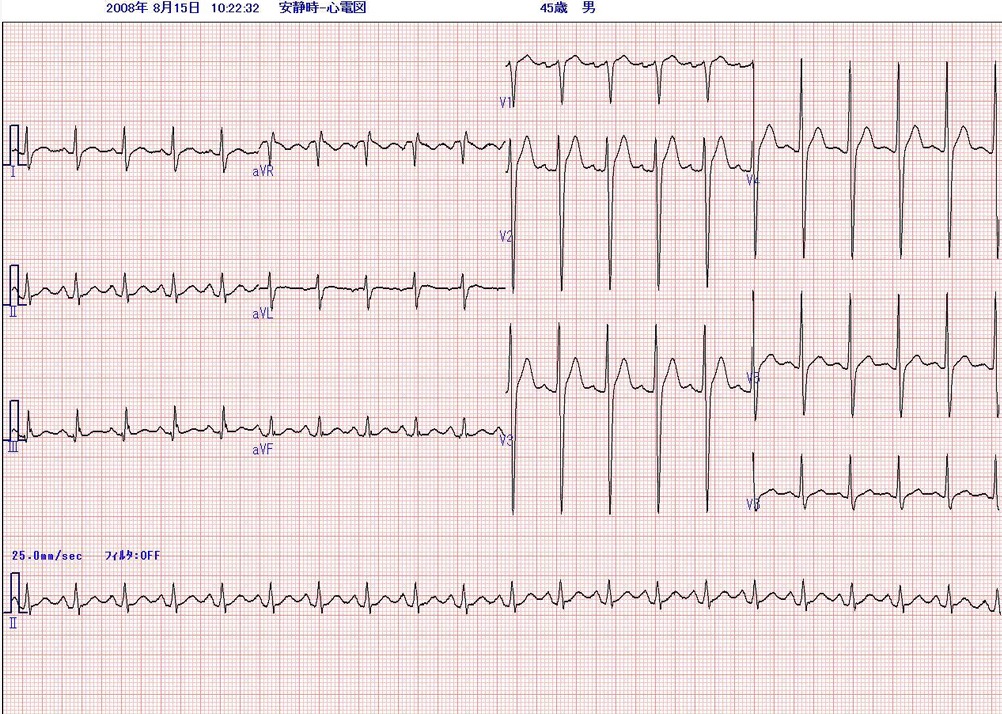

来院時にとられた心電図(1)と6年前に胆嚢炎で入院した時の心電図(2)を示します。

心電図(2)6年前

心電図(2):洞頻脈、その他に異常なし

ここで5年前にとられた心電図(2)をみると、洞頻脈であるが、それ以外に特に異常はみられない。たった5年の間に何がおこったのであろうか。

両者の比較で、5年の間に、①QRS voltageが全体に低下した、②胸部誘導でr波が明らかに減少した(陳旧性前壁中隔梗塞様所見)、③心室内伝導遅延がおこっている、④非特異的STT異常が認められる。 病歴から過去に心筋梗塞を起こした様子はない。受診時の血圧は102/76mmHgと低下している。急激に進行する左心不全と左室電位の低下、心室内での瀰漫性の伝導障害を総合すると、過去5年間に心臓全体に変性病変が起こり心機能が低下したことが考えられる。